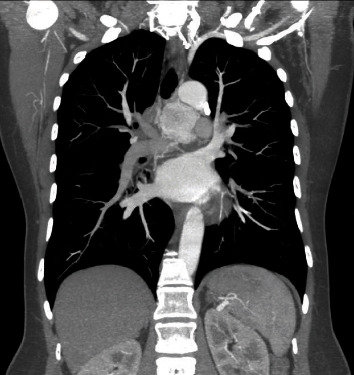

Paraganglioma of the middle mediastinum has a prevalence of 1%-2% of paragangliomas and less than 1% of mediastinal masses. It is generally asymptomatic and can easily be confused with other pathologies. The following is the case of a 50-year-old patient who, as an incidental finding, documented an injury between the aorta and the pulmonary artery, hypervascularized, which was embolized prior to surgery, which facilitated the complete resection of the lesion by sternotomy. With favorable evolution of the patient and discharge on the fourth postoperative day. A thorough review of the literature on the diagnostic and treatment approach to this pathology has been also carried out.

中纵隔副神经节瘤的发病率为副神经节瘤的 1%-2%,不到纵隔肿块的 1%。它一般没有症状,很容易与其他病变混淆。以下是一名 50 岁患者的病例,他偶然发现主动脉和肺动脉之间有损伤,血管扩张,手术前对其进行了栓塞,这有助于通过胸骨切开术完全切除病灶。术后第四天,患者康复出院。此外,还对该病症的诊断和治疗方法进行了全面的文献综述。